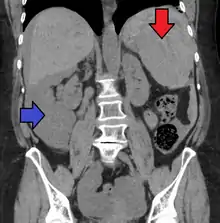

Splenic hematoma resulting in free abdominal blood